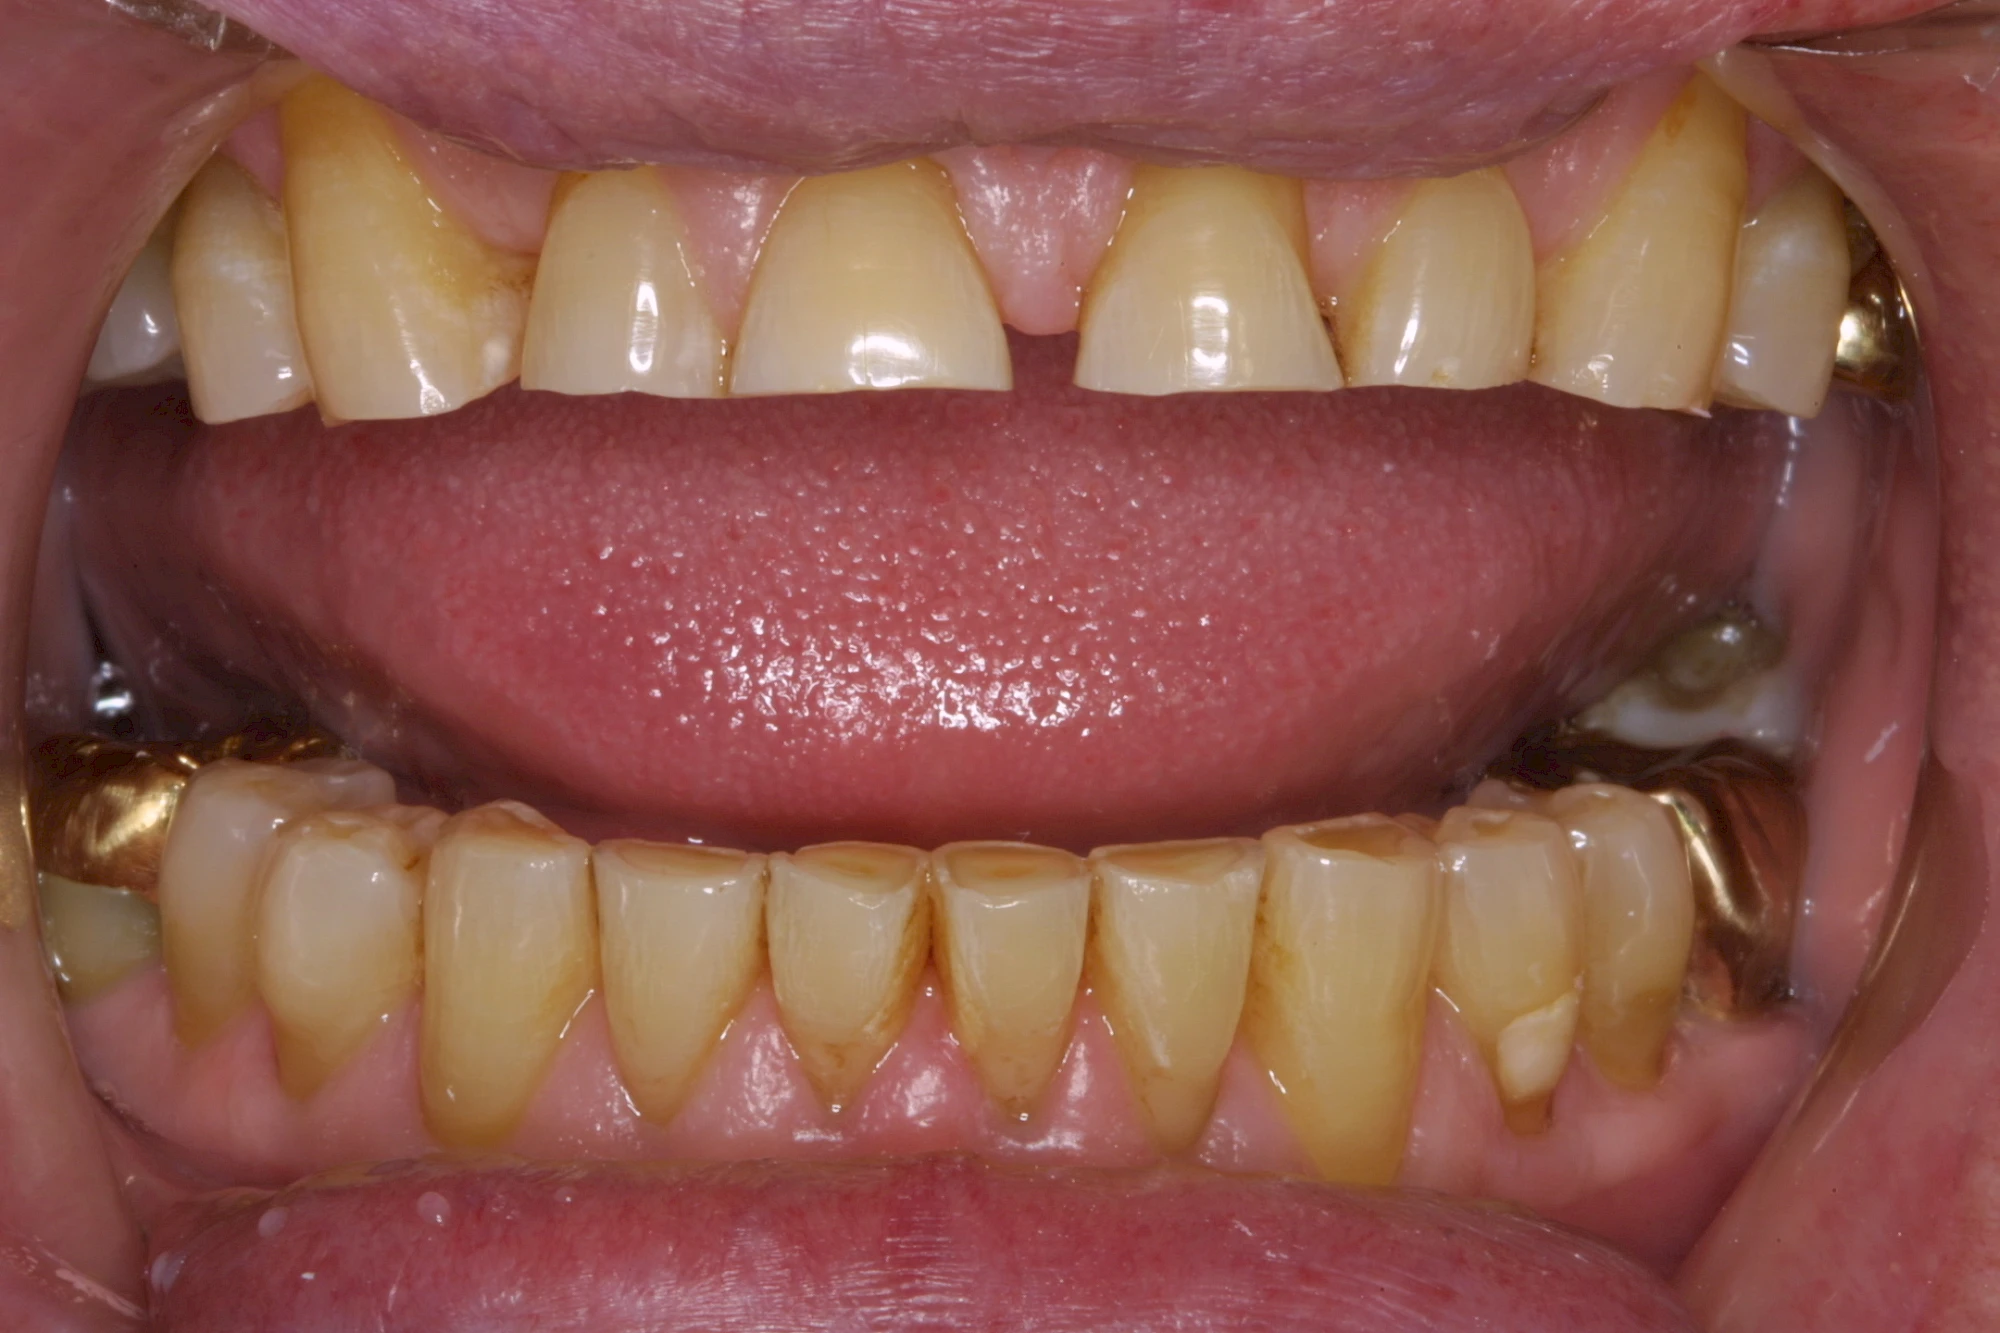

Über die Zeit können verschiedene Prozesse die Zahnhartsubstanzen aufzehren:

- Abnutzung durch Kauen (Abrasion) oder duch durch übermäßiges Knirschen bzw. Pressen (Attrition)

- Säurebedingte Auswaschung (Erosion)

- Knirschen bzw. Pressen und ungünstige Putztechnik (Druck): keilförmige Defekte

Die Zähne können dabei auf Reize (warm, kalt, süß, sauer) oder auch beim Zähneputzen empfindlich oder schmerzhaft sein. In allen diesen Fällen ist es sinnvoll, den Zahnarzt zu kontaktieren und das weitere Vorgehen abzustimmen.